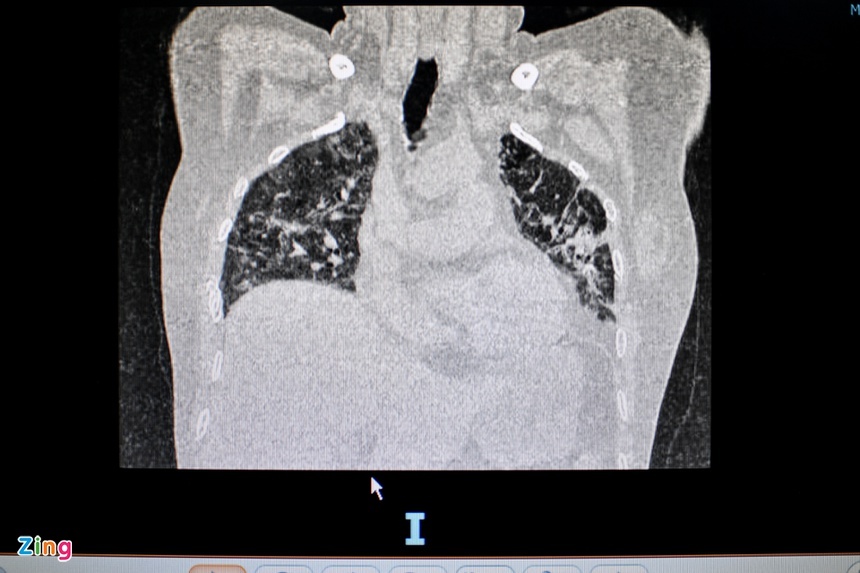

Hình chụp X-quang của bệnh nhân sau một năm khỏi Covid-19 xuất hiện các bất thường trên phổi. Ảnh: Respiratory Research.

Các biến chứng này có thể quan sát được sau 3-6 tháng kể từ khi khỏi bệnh, tùy theo các mức độ nghiêm trọng khác nhau như suy giảm chức năng, khó thở… Tuy nhiên, nghiên cứu được công bố trên tạp chí Respiratory Research cuối tháng 3 cho thấy trên hình chụp X-quang của bệnh nhân sau một năm khỏi Covid-19 vẫn xuất hiện các bất thường trên phổi. Dù vậy, phổi bị xơ hóa là tình trạng không phổ biến ở người khỏi Covid-19. Chỉ 1% bệnh nhân có biến chứng này sau 12 tháng kể từ khi xuất viện.